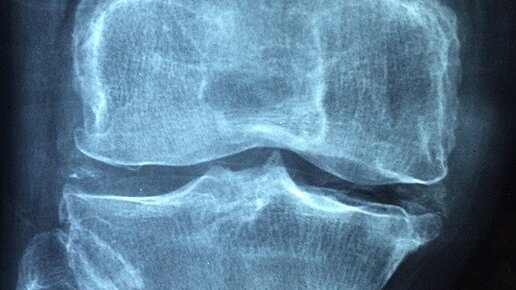

Больные суставы – это не только проблема стариков. Много молодых людей сталкивается с подобной проблемой из-за многих причин: плохая экология, наследственность, заболевания, физические нагрузки и так далее. Питание играет ключевую роль в здоровье суставов, потому что из пищи организм получает строительные материалы для костей и хрящей. В этой заметке названы продукты, которые очень вредны для суставов. Что не любят суставы Если в суставах появился хруст, дискомфорт или боль, то пересмотрите свой рацион...

Боли в суставах могут возникать по причине различных воспалительных процессов, полученных травм, растяжений, а так же из-за отложения солей. Проблемами с суставами страдает примерно половина человечества...